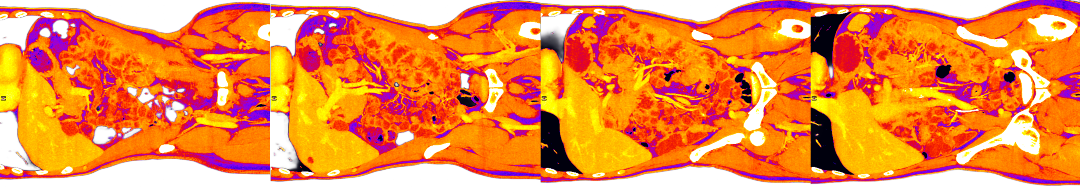

A PET scan is organised a few days later, at St Barts Hospital, in the shadow of St Paul’s. The body is flooded with a tracer radioactive fluid, after which you are locked into a lead-lined box for three-quarters of an hour to allow it to bake in. The scanner then detects where the tracer has been absorbed by cell growth anywhere in the body it is directed, producing reams of flowing light captured to film, copies of which—scans of my own body—are used throughout this post.

On seeing further scans, I recognised, eg., my rib cage as something indeed very much like the frame of Israel’s tents (above, top left), beaming on the shore of the infinite (Blake), but also, in the twisting images of the torso, I am struck by the sprawling energies at play, unleashed by disease. No longer is there the assumed underlying durable person, sealed away from the totality, cybernetically establishing their personal border by fending off and repurposing the chaos, sickness and disorder without. Instead, raw energies start to coalesce, turning Urizenic, mechanical rigidity into flashes, streaks and pulses of contending light.

When looking at the flowing lights of the scans, I am not seeing the regular mechanics/dynamics of fluid flow and the like. It is not the competing power of the different forces involved, sloshing against one another, that impresses. That would represent a reasonable romantic regard for the power of things we don’t fully understand, and which we dimly suspect may outbid us in the end.

What I find more compelling in the forms on show are the signs of a deeper, primordial language of the cosmos, God’s being and the unconstrained underpinning of all those other things, the syntax of God’s mind and its reality of eternal esemplatic (form-giving, creative) inflation. To see the churning faces of the sea of light is to see the surface of the esemplasm that is all being, and which calls us from its depths.